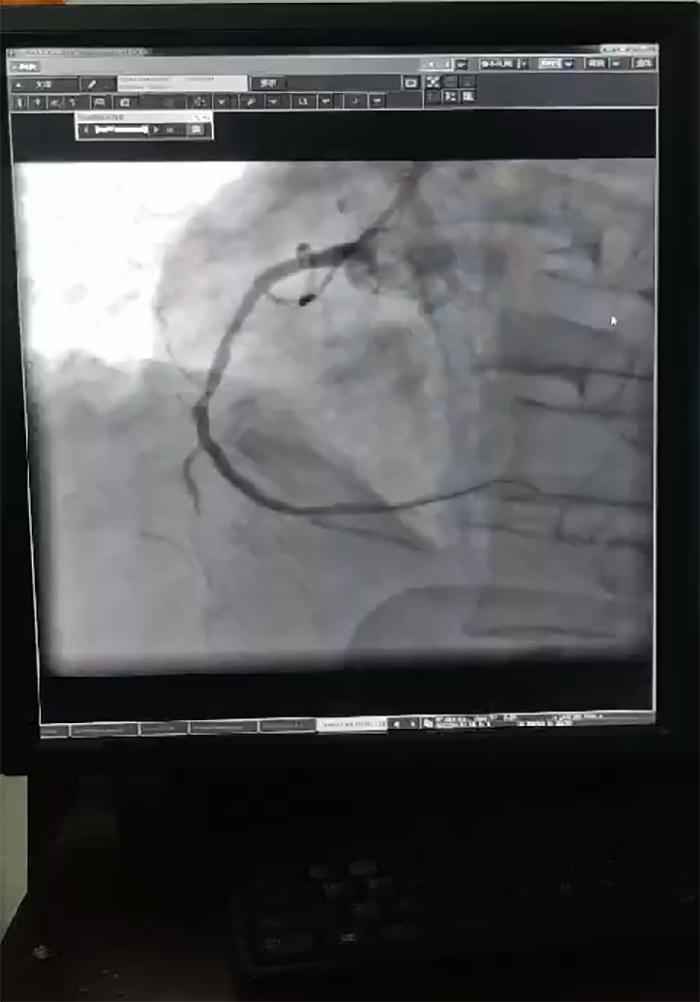

“在冠状动脉造影术下,显示患者心脏左主干加上三支血管病变,这种情况基本属于九死一生。”91club 心血管内科主任蔡亚滨介绍,多学科联合抢救团队马上确定救治方案,ICU团队先上V-A ECMO(体外膜肺氧合技术,起到一个人工心肺的作用)稳定患者状况,随后心血管内科介入团队在ECMO保护下进行介入手术(PCI),在患者左主干前降支、回旋支、右冠植入支架,90分钟后顺利完成手术。术后第4天,患者心率、血压稳定,顺利拔除ECMO动静脉导管,术后第10天转入普通病房继续诊治。